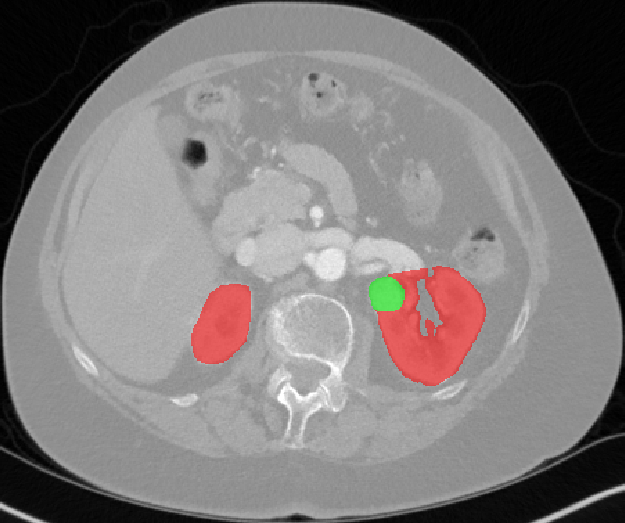

Edge-Aware 3D Image Segmentation Networks

[91]: Automated segmentation of kidneys and kidney tumors is an important step in quantifying the tumor’s morphometrical details to monitor the progression of the disease and accurately compare decisions regarding the kidney tumor treatment. Manual delineation techniques are often tedious, error-prone and require expert knowledge for creating unambiguous representation of kidneys and kidney tumors segmentation. We propose a 3D end-to-end edge-aware FCN for reliable kidney and kidney tumor semantic segmentation from arterial phase abdominal 3D CT scans. Our segmentation network consists of an encoder-decoder architecture that specifically accounts for organ and tumor semantics. We evaluate our model on the 2019 MICCAI KiTS Kidney Tumor Segmentation Challenge dataset. -